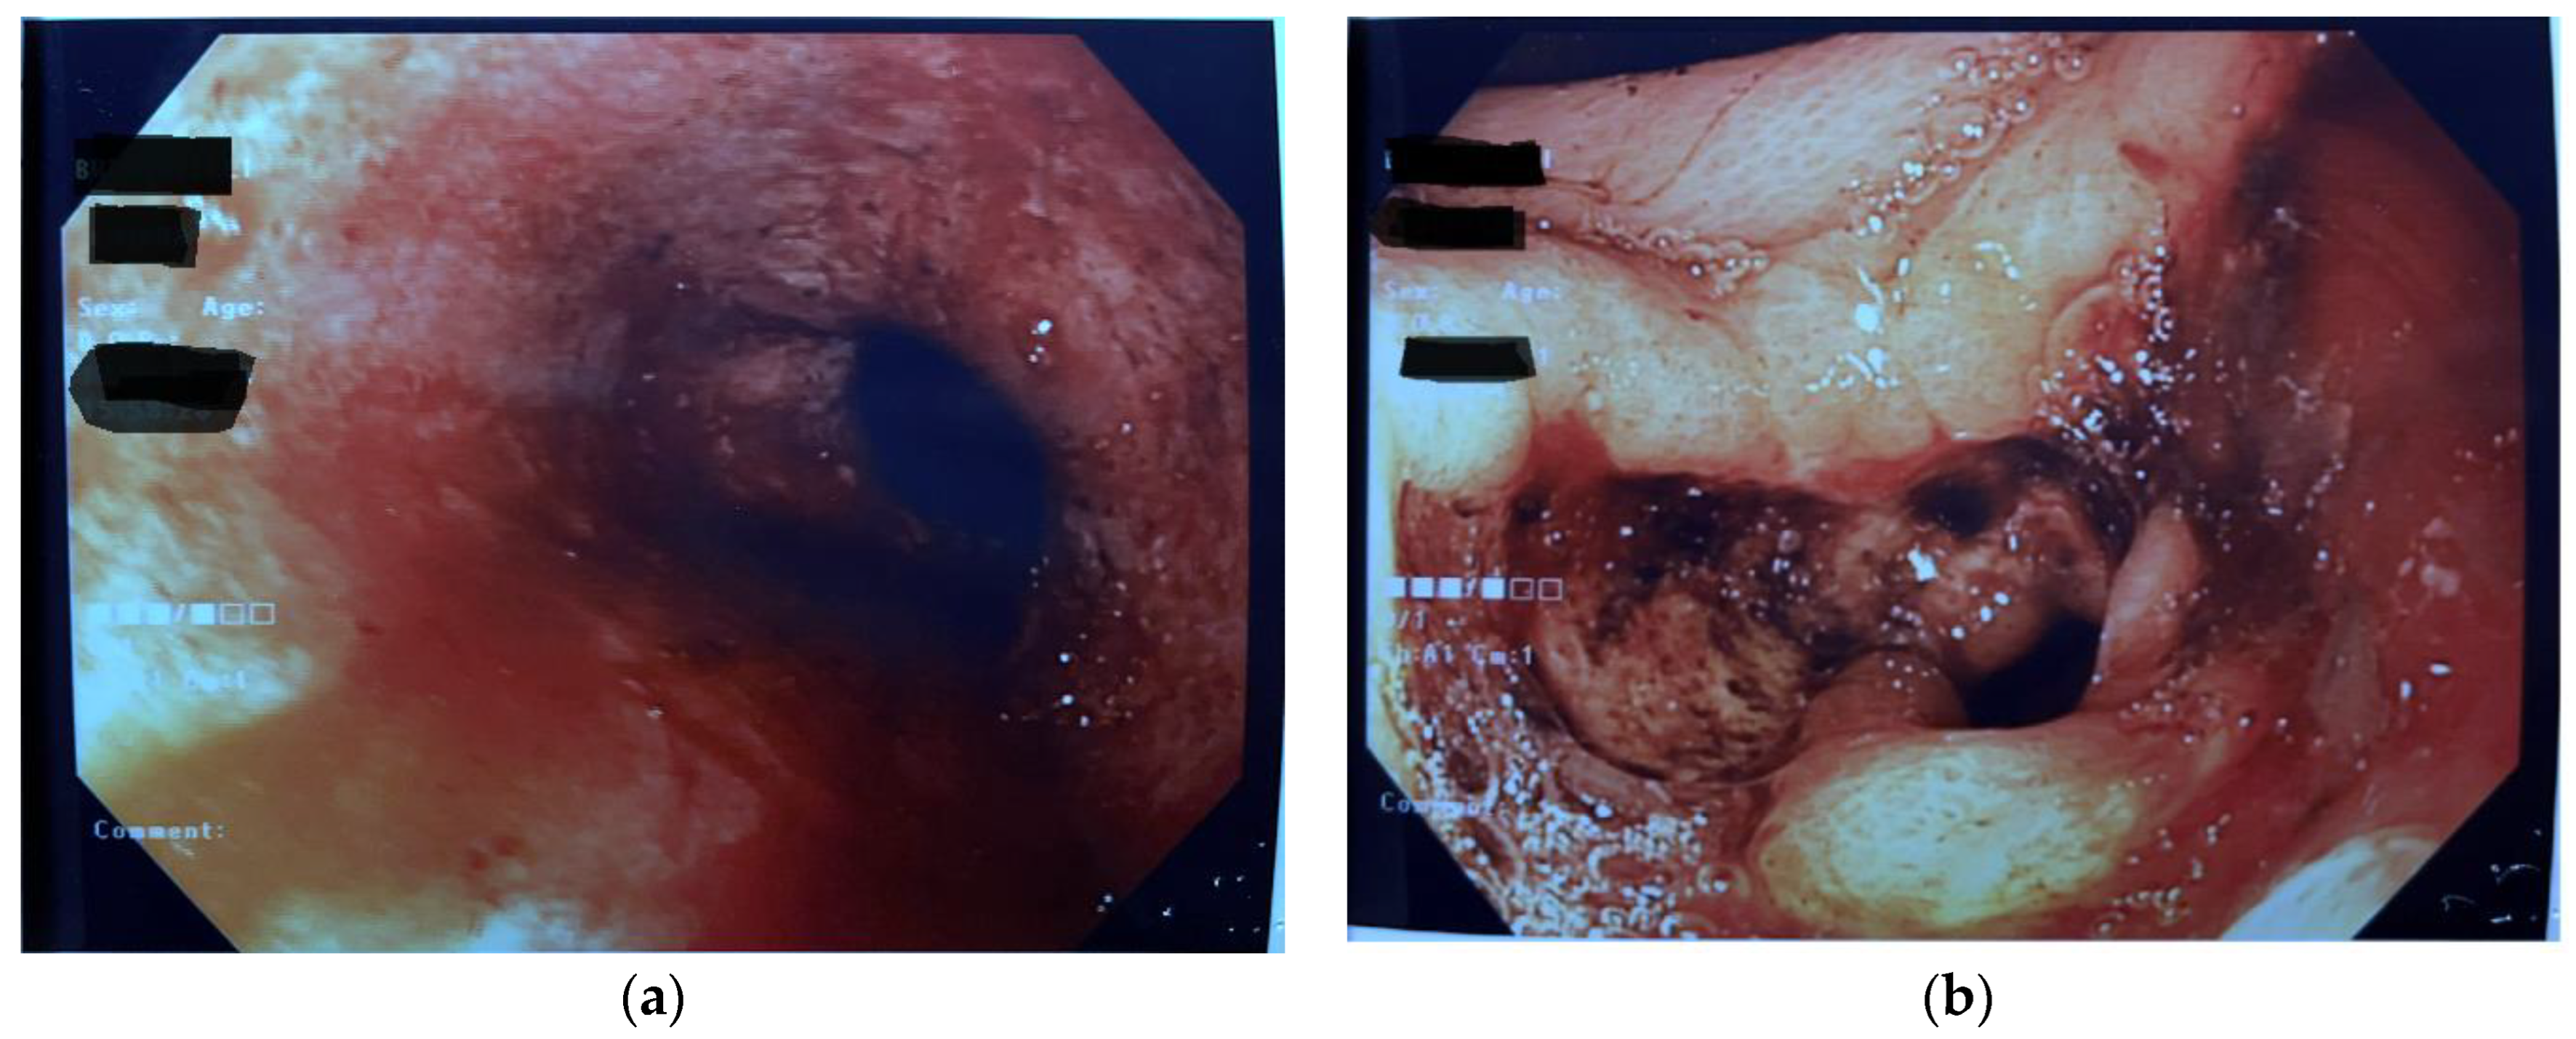

Abstract

1. Introduction

2. Discussion